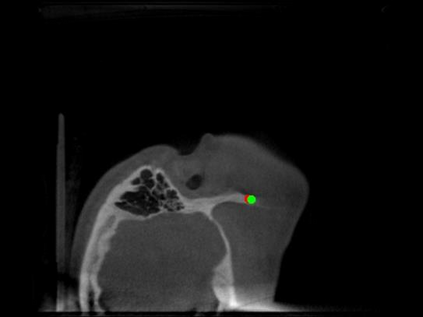

Detecting 3D landmarks on cone-beam computed tomography (CBCT) is crucial to assessing and quantifying the anatomical abnormalities in 3D cephalometric analysis. However, the current methods are time-consuming and suffer from large biases in landmark localization, leading to unreliable diagnosis results. In this work, we propose a novel Structure-Aware Long Short-Term Memory framework (SA-LSTM) for efficient and accurate 3D landmark detection. To reduce the computational burden, SA-LSTM is designed in two stages. It first locates the coarse landmarks via heatmap regression on a down-sampled CBCT volume and then progressively refines landmarks by attentive offset regression using multi-resolution cropped patches. To boost accuracy, SA-LSTM captures global-local dependence among the cropping patches via self-attention. Specifically, a novel graph attention module implicitly encodes the landmark's global structure to rationalize the predicted position. Moreover, a novel attention-gated module recursively filters irrelevant local features and maintains high-confident local predictions for aggregating the final result. Experiments conducted on an in-house dataset and a public dataset show that our method outperforms state-of-the-art methods, achieving 1.64 mm and 2.37 mm average errors, respectively. Furthermore, our method is very efficient, taking only 0.5 seconds for inferring the whole CBCT volume of resolution 768$\times$768$\times$576.